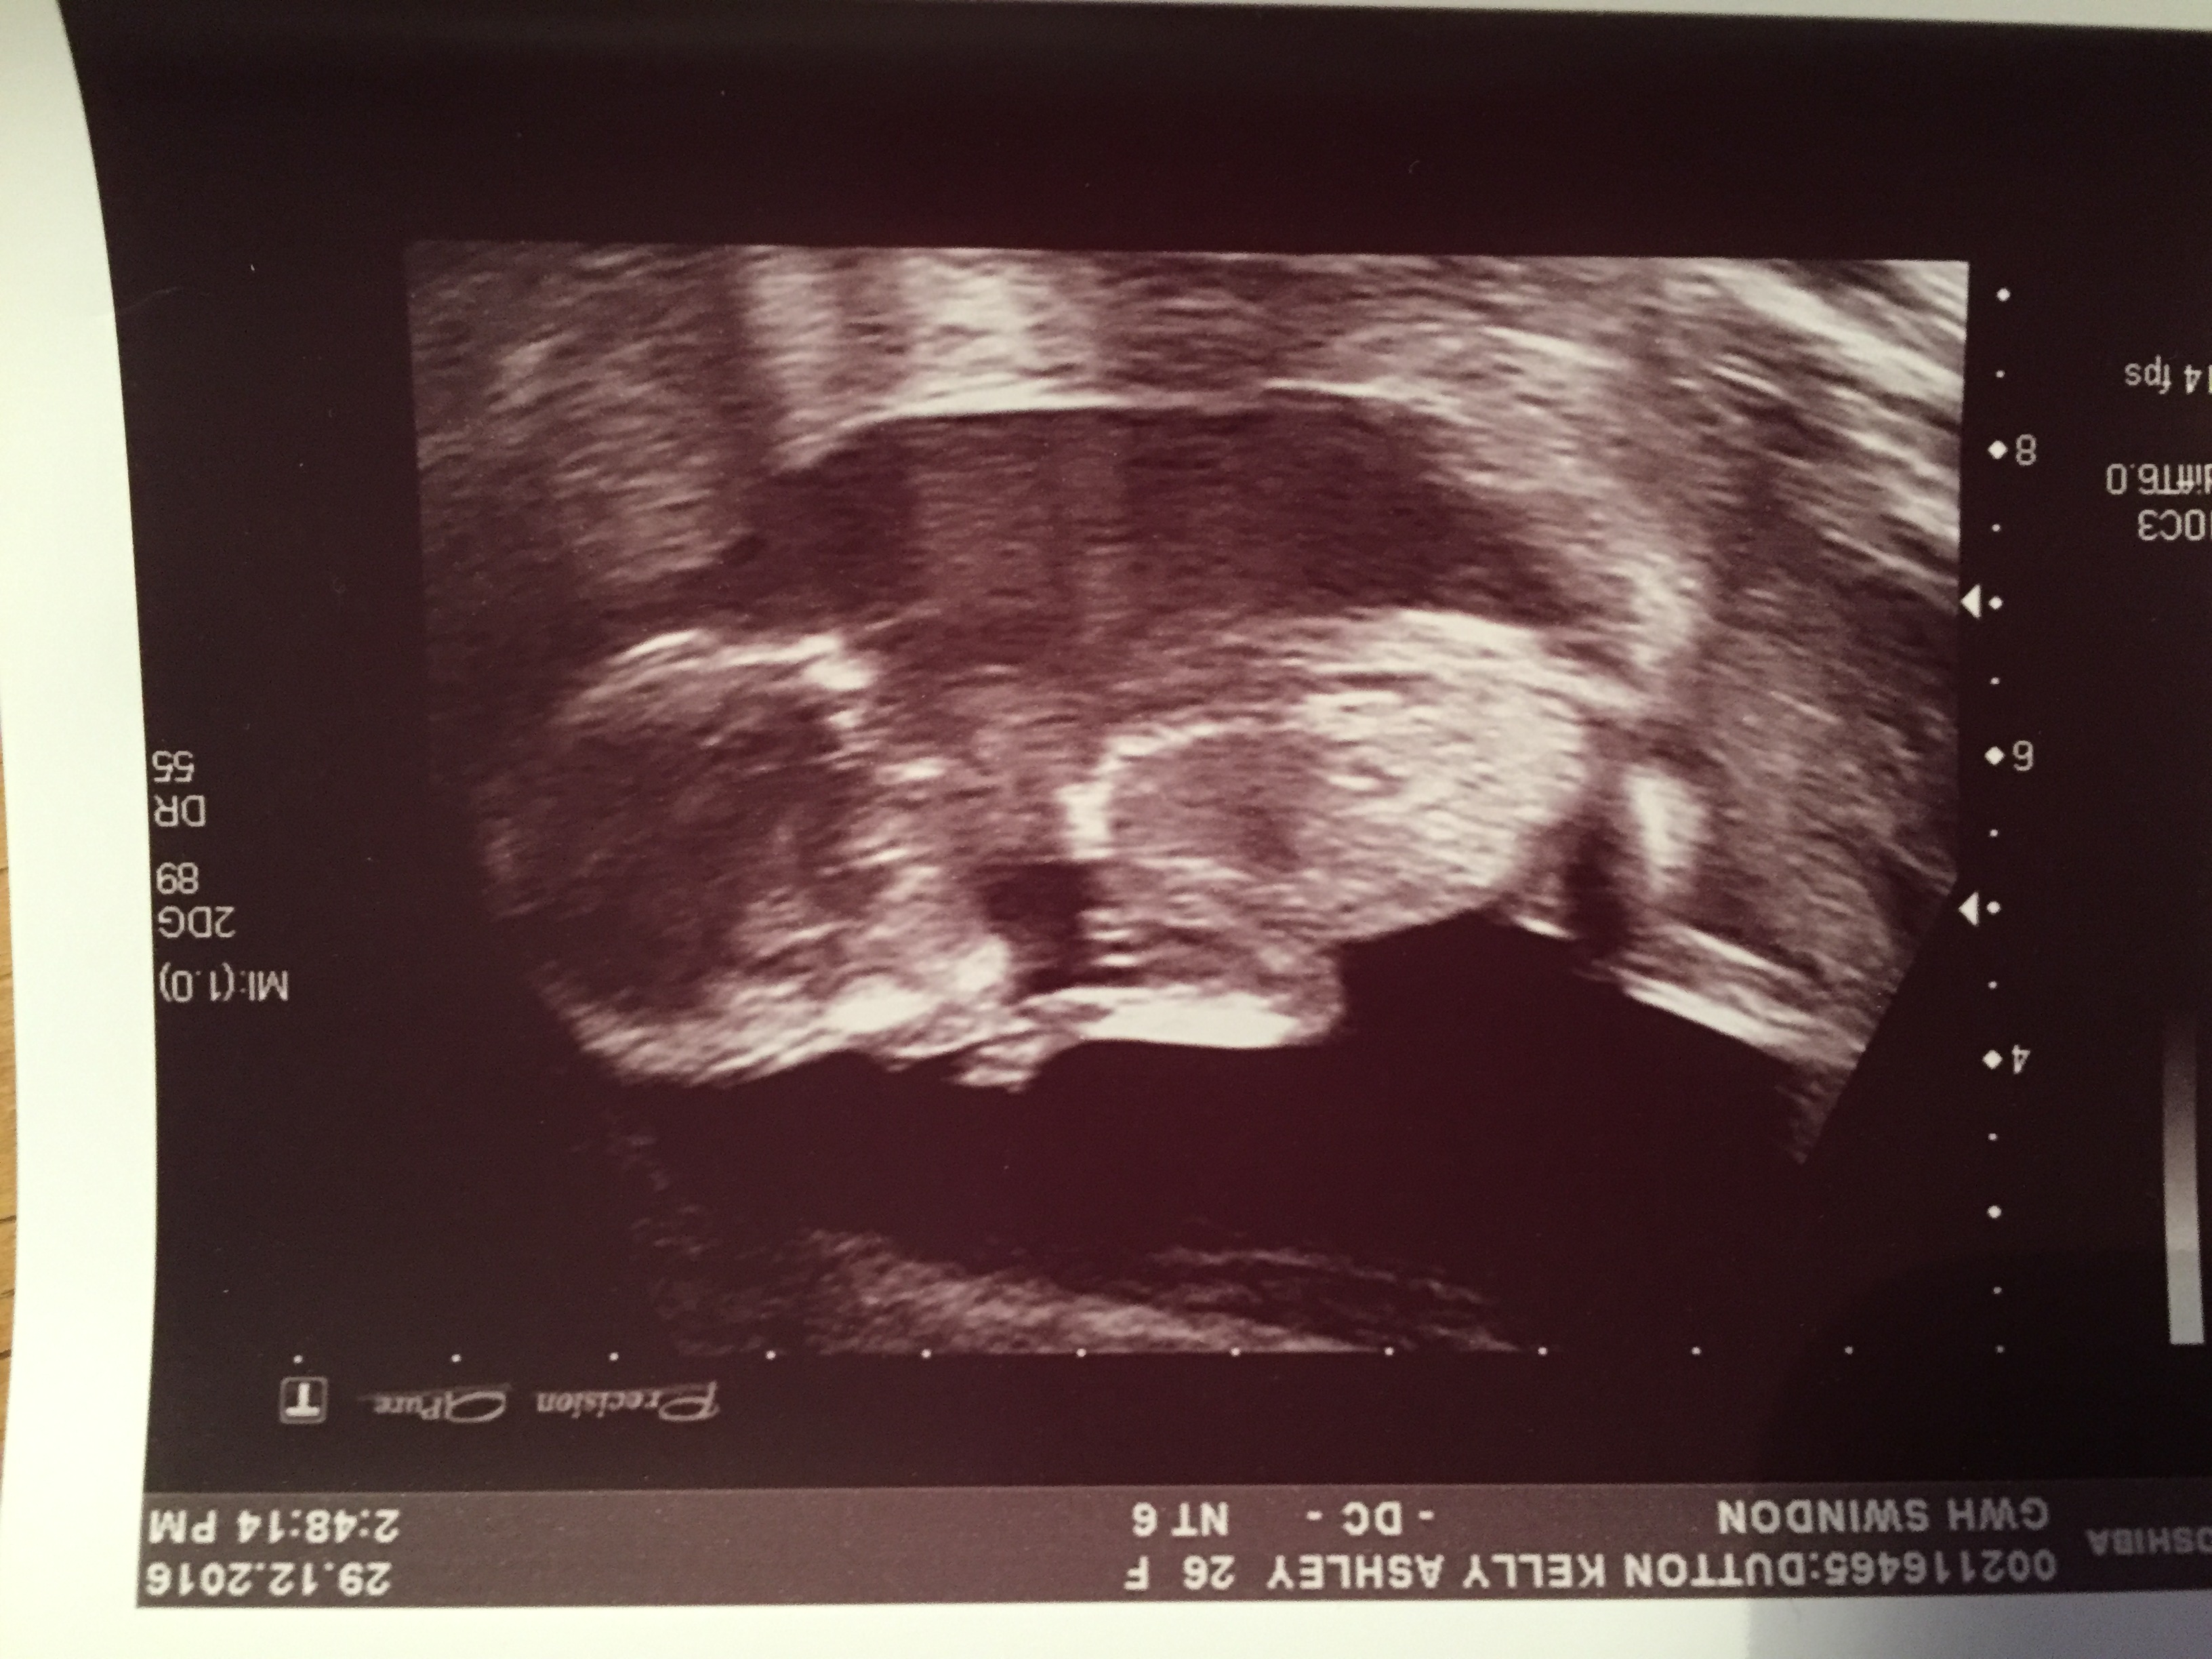

Just found this great forum and wondered if anyone could give an opinion from our 16 week ultrasound.

Am going girl also. The earlier photo in one there looks like a long flat white line parallel with the spine, indicates girl. There is also something under it that looks like a forked nub, which again would suggest girl. Not sure which is the nub but both indicate girl. Unless anyone thought it was stacking? But I don't think so x

Hi, a wee update for all those that guessed, was at hospital today and confirmed a girl, so good work.